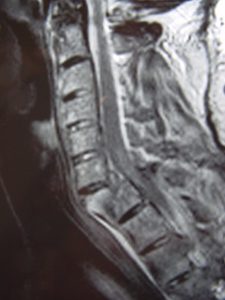

Εικόνα 2 (α,β,γ,δ,ε) Προεγχειρητική Μαγνητική Τομογραφία Α.Μ.Σ.Σ. – Ακολουθία Τ2 και Τ1 Οβελιαία τομή (Sagittal) λίγες ώρες μετά το ατύχημα. Η βλάβη ξεκινά από οπίσθια συνδεσμο-οστικά στοιχεία στο επίπεδο Α6-Α7 και περνά προσθίως μέσα από τον Μεσοσπονδύλιο Δίσκο και την πρόσθια κολόνα του 7ου αυχενικού σπονδύλου. Παρατηρείται μετατραυματικό οίδημα του νωτιαίου μυελού στο σύστοιχο επίπεδο.